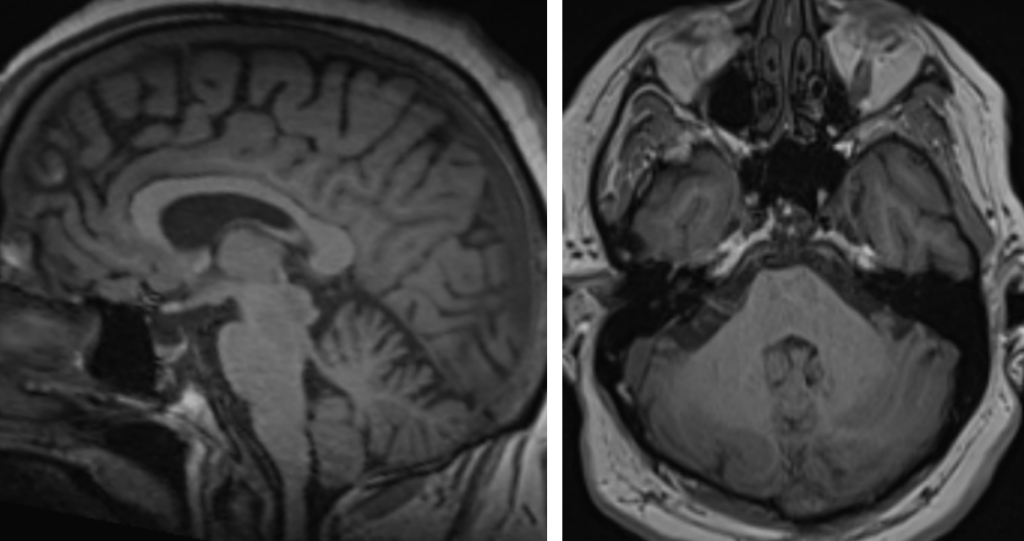

Figura 2: examinare IRM sagital şi axial T1

Discuţie caz nr 45: Chisturile neuroenterice sunt leziuni de dezvoltare care au origine din endoderm, cel mai frecvent întâlnite în canalul rahidian, dar observate și în fosa posterioară și mai rar, supratentorial.